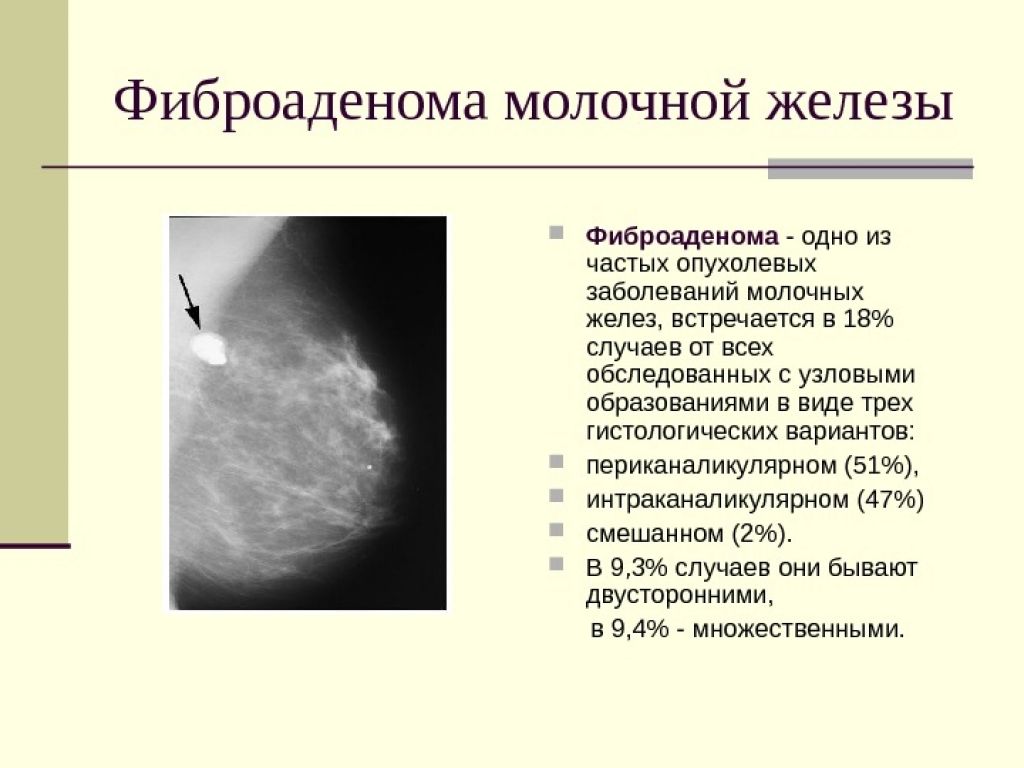

Новообразование в головном мозге. Презентация опухоль мозга. Опухоли головного мозга презентация. Злокачественная фиброаденома молочной железы. Фиброаденома молочной железы Размеры для операции. Фиброаденома молочной железы маммография. Листовидная опухоль гистология.

Злокачественная фиброаденома молочной железы. Фиброаденома молочной железы Размеры для операции. Фиброаденома молочной железы маммография. Листовидная опухоль гистология. Доброкачественная опухоль. Доброкачественныеопкхоли. Клетки, образующие доброкачественную опухоль:. Строение доброкачественной опухоли.

Подчелюстная слюнная железа на рентгене. Сиалография слюнных желез. Рентгенография слюнных желез. Контрастная сиалография слюнных желез. Фиброаденома молочной железы дифференциальный диагноз. Новообразование молочной железы фиброаденома. Диф диагноз фиброаденомы молочной железы. Фиброаденома молочной железы 30мм-37мм.

Фиброаденома молочной железы дифференциальный диагноз. Новообразование молочной железы фиброаденома. Диф диагноз фиброаденомы молочной железы. Фиброаденома молочной железы 30мм-37мм. Диагностические критерии глиомы головного мозга. Особенности опухолей лобной доли. Клиника опухоли затылочной доли головного мозга. Симптомы, характерные для опухолей лобной доли.